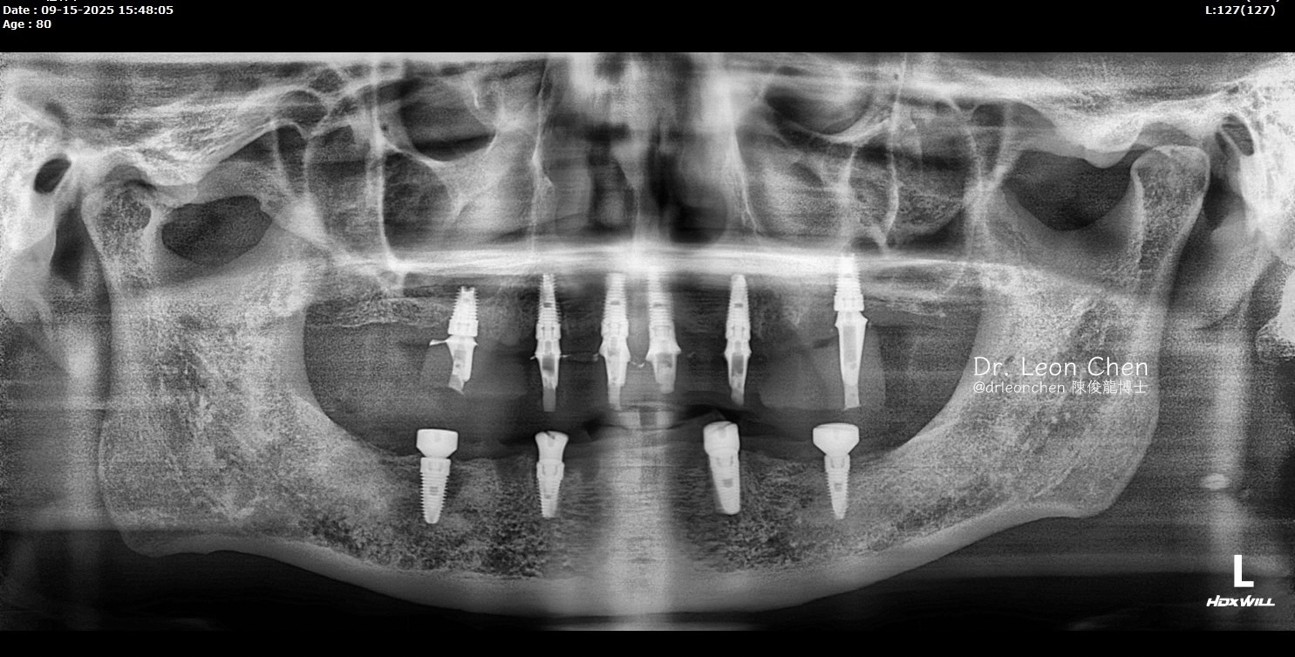

精奈創一鑽植牙系統團隊|改變80歲好朋友的決定!

有一位臨時走進診所,要做全口植牙的新病人。預約回診當天,他特地帶了小學的好朋友一起來,這位朋友也有全口植牙的需求。

病人因為對手術結果非常滿意,就推薦好友一起來找陳博士治療。

他的朋友原本覺得自己都80歲了,不需要再做什麼改變。但看到好友做完全口植牙後開心的樣子,他也心動了。

雖然一開始他哭喊著「都80歲了、沒有錢啦」,最後選擇最基本的方案治療。

一週後他再回來診所,詢問上下顎可以再多植幾顆嗎?陳博士回答:「當然可以。」

「陳俊龍博士整套 LEONS Concept 精奈創一鑽植牙」技術手術少,創傷小,恢復快!

沒有併發症;適合各類患者,不用停藥,也可以接受治療。